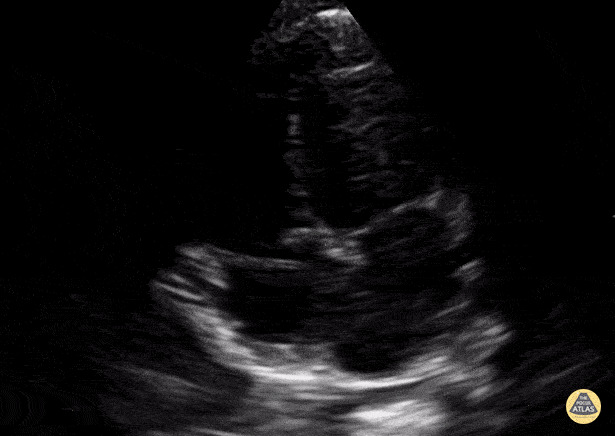

Normal Toddler Apical 4 chamber. Contributor: Jaron Smith, MD, Phoenix Children's Hospital

View: Unspecified Parasternal Long Axis Parasternal Short Axis Apical Four-Chamber Subcostal Four-Chamber Subcostal Inferior Vena Cava Right Upper Quadrant Left Upper Quadrant Suprapubic Longitudinal Suprapubic Transverse Subxiphoid Anterior Thoracic Phrenic